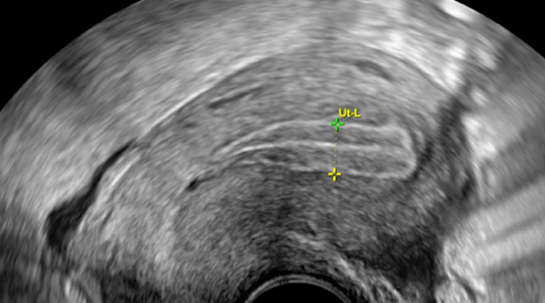

Trilaminares Endometrium

Dominater Follikel